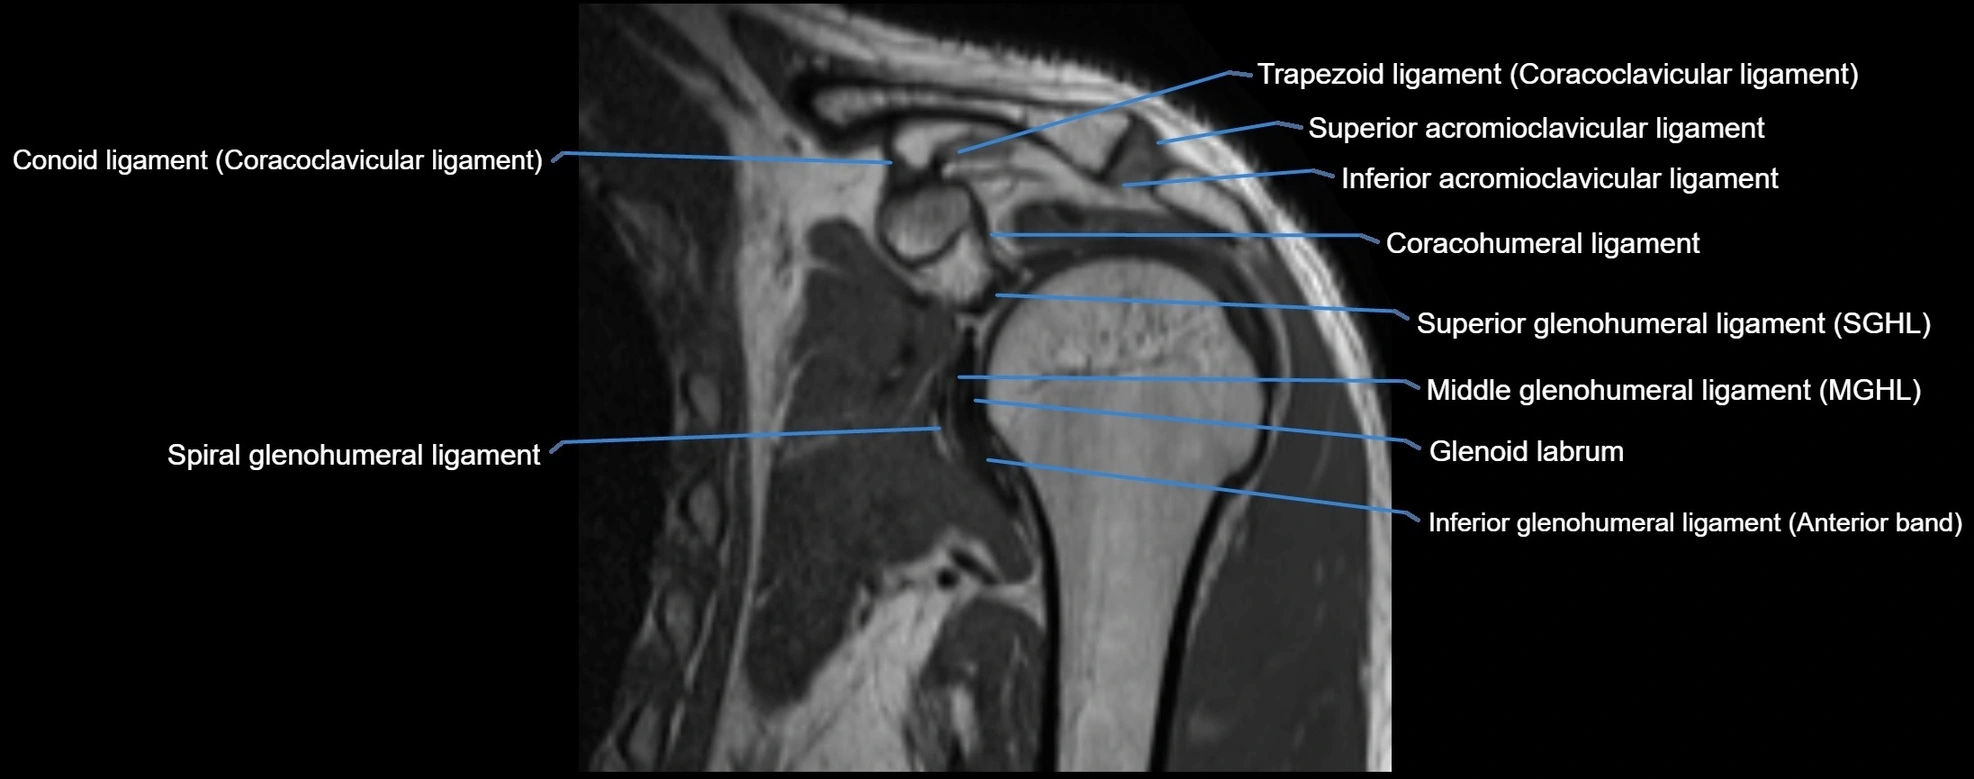

MRI images

image